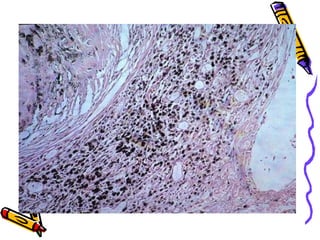

Microscopy

• Concentric hyalinized collagen

surrounded by condensed

collagen,fibroblasts & lymphocytes.

• Birefringent silica particles

(polarized light)

• Nodules incorporate normal lung

tissue into themselves.